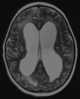

Transependymal CSF flow

Normal-pressure hydrocephalus (NPH), also called malresorptive hydrocephalus, is form of communicating hydrocephalus in which excess cerebrospinal fluid (CSF) occurs in the ventricles, and with normal or slightly elevated cerebrospinal fluid pressure. As the fluid builds up, it causes the ventricles to enlarge and the pressure inside the head to increase, compressing surrounding brain tissue and leading to neurological complications. [Source: Wikipedia ]